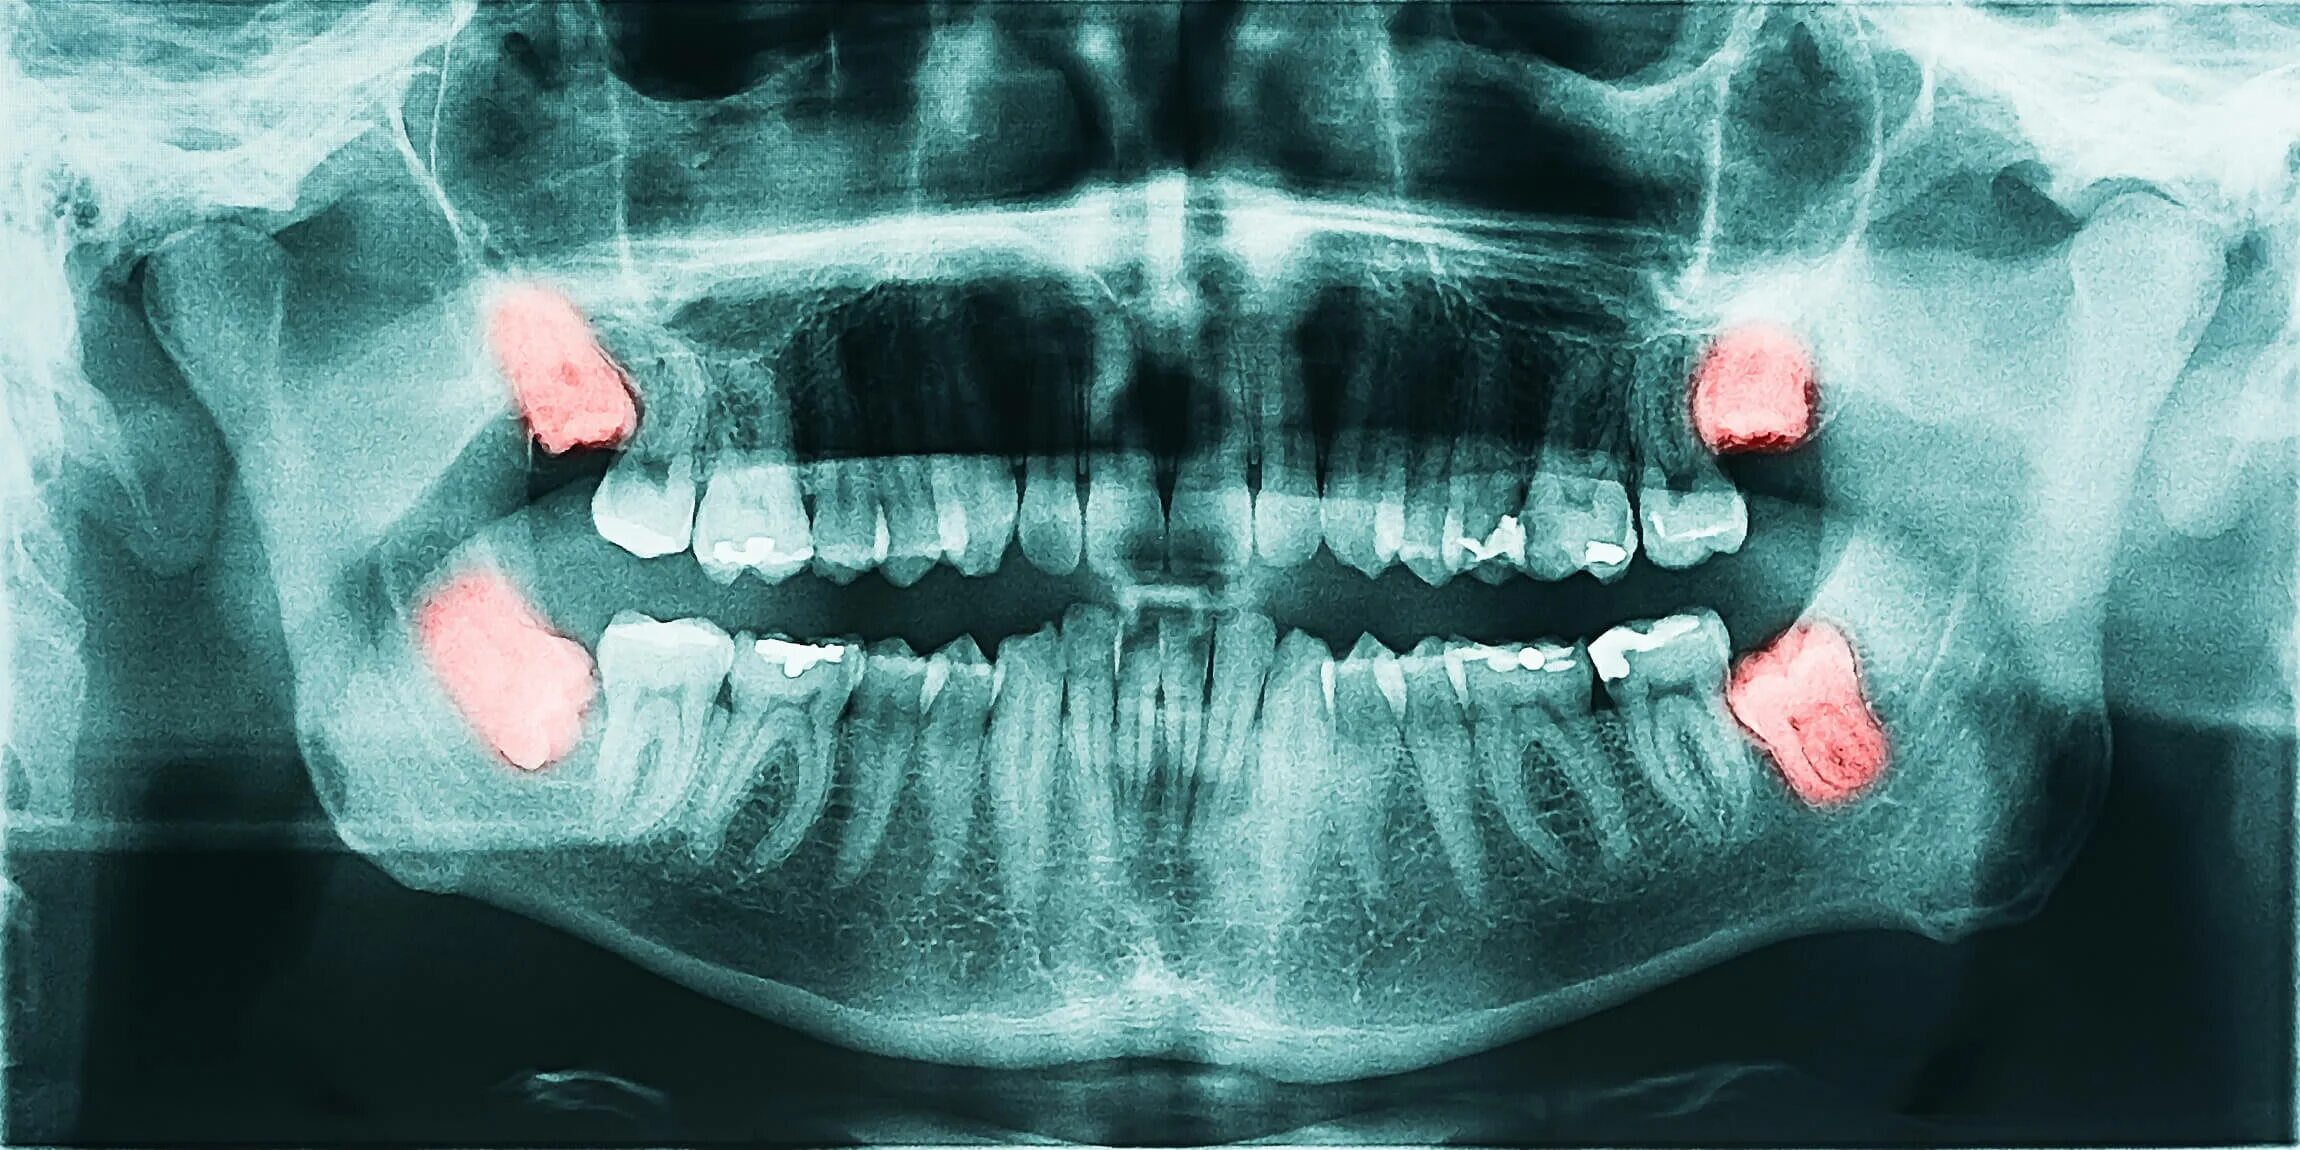

Болит вся челюсть и все зубы